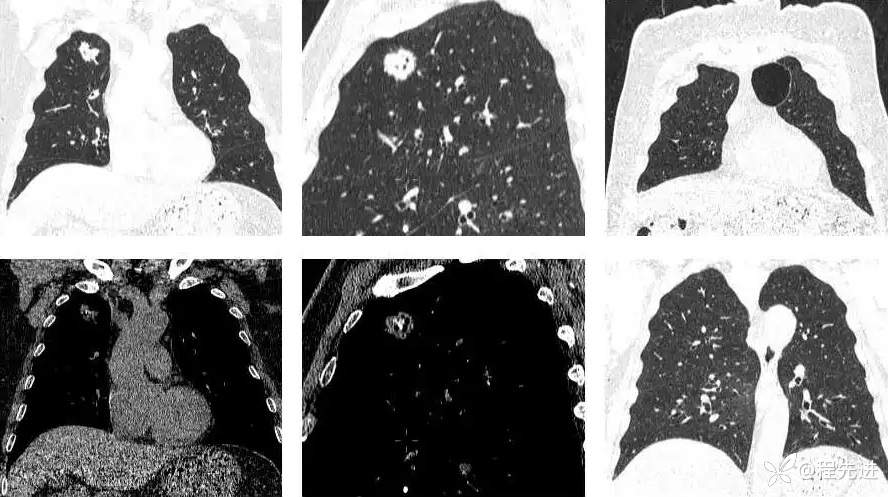

CT平扫:

上排与上面同时间,下排是3月后复查